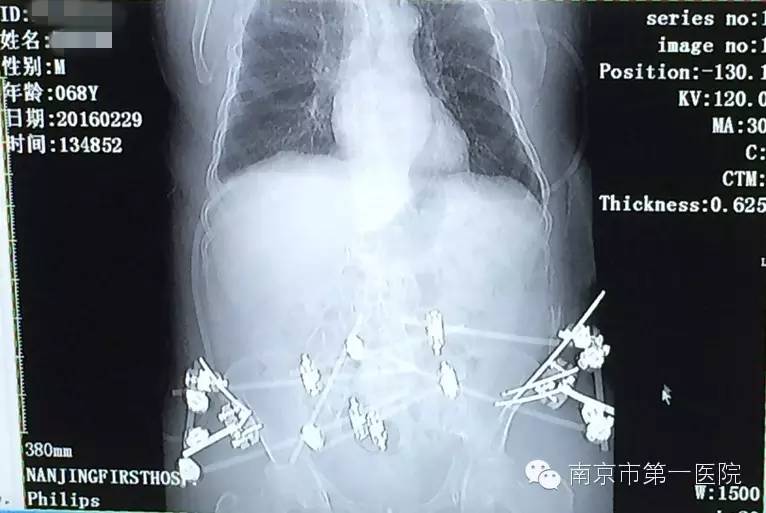

我院骨科专家梁斌接到通知后,开通多发伤绿色通道,迅速召集科内骨干医生进行术前讨论、制定手术计划。考虑到患者创伤严重、出血量大,必须最大程度地减少手术伤口,梁主任决定立刻采取微创技术进行骨盆闭合复位支架外固定术。

术中,主刀医生操作技术娴熟,争分夺秒,有条不紊地进行着各项操作。经过1个小时,手术顺利结束,成功修复了患者重度骨折的骨盆。据悉,整个手术过程中,创伤小、出血量低,切口大小也仅有1-2cm左右。